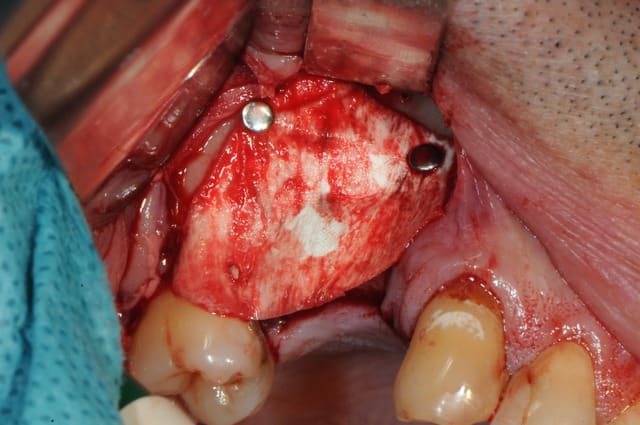

en attendant voici un des deux sinus de ce matin.

MP3 ( chez Pred) en comblement et ROG avec membrane et pins pour palier la forte concavité vestibulaire.

ps: je mets ces photos surtout parce que c'est rigolo de demander au patient de faire bouger sa membrane sinusienne...